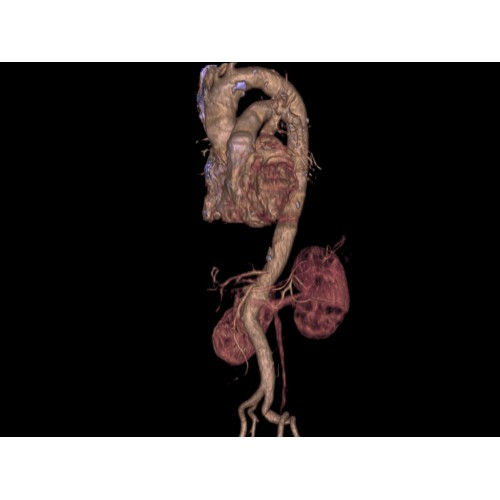

Позволяет проводить комплексные исследования всех анатомических зон, включая нейровизуализацию, ангиографию, исследования органов грудной и брюшной полости. Особенно эффективен для раннего выявления онкологических заболеваний.